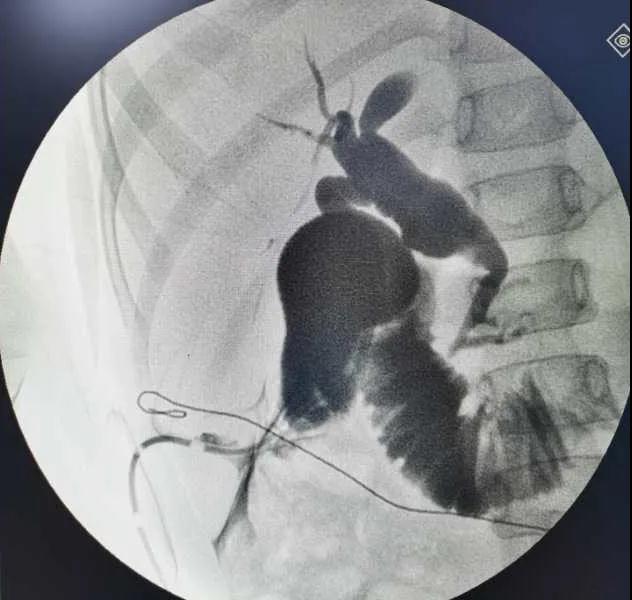

5月7日,西安國(guó)際醫(yī)學(xué)中心醫(yī)院小兒外科郭正團(tuán)教授團(tuán)隊(duì)成功為1名膽總管囊腫患兒進(jìn)行了腹腔鏡膽管造影 腹腔鏡膽總管囊腫切除 腹腔鏡肝管空腸吻合術(shù)。目前,患兒恢復(fù)良好,已正常進(jìn)食。

入院后,謝崇醫(yī)生積極為患兒完善術(shù)前準(zhǔn)備,MRCP(核磁共振膽道水成像)顯示該患兒為膽總管囊腫Ic型,有明顯的胰膽合流異常。面對(duì)復(fù)雜的病情,小兒外科郭正團(tuán)主任立即組織團(tuán)隊(duì)進(jìn)行術(shù)前討論,制定了完善的手術(shù)方案及應(yīng)急措施。

“Ic型膽總管囊腫往往以慢性腹痛為主要臨床表現(xiàn),易誤診漏診,一部分病人直到成人時(shí)才發(fā)現(xiàn),肝功能進(jìn)行性損害,遠(yuǎn)期癌變風(fēng)險(xiǎn)大。該患兒胰膽合流異常,主胰管及副胰管均異常匯入膽總管,增加了切除胰腺段膽管的風(fēng)險(xiǎn),但我們有信心有能力完成此次手術(shù),佑護(hù)患兒健康。”郭正團(tuán)主任說。

5月7日,一切準(zhǔn)備就緒,郭正團(tuán)主任主刀,帶領(lǐng)小兒外科團(tuán)隊(duì)進(jìn)行腹腔鏡膽管造影 腹腔鏡膽總管囊腫切除 腹腔鏡肝管空腸吻合術(shù)。術(shù)中,患兒膽總管與周圍肝動(dòng)脈及門靜脈粘連嚴(yán)重,給手術(shù)增加了難度。郭正團(tuán)主任沉著冷靜,操作嫻熟,完整剝離了膽總管囊腫及遠(yuǎn)端胰腺段膽管,肝總管與空腸完成了Roux-en-Y吻合,手術(shù)進(jìn)行順利。術(shù)后第2天,玲玲就可以下床活動(dòng);第6天,已正常飲食。